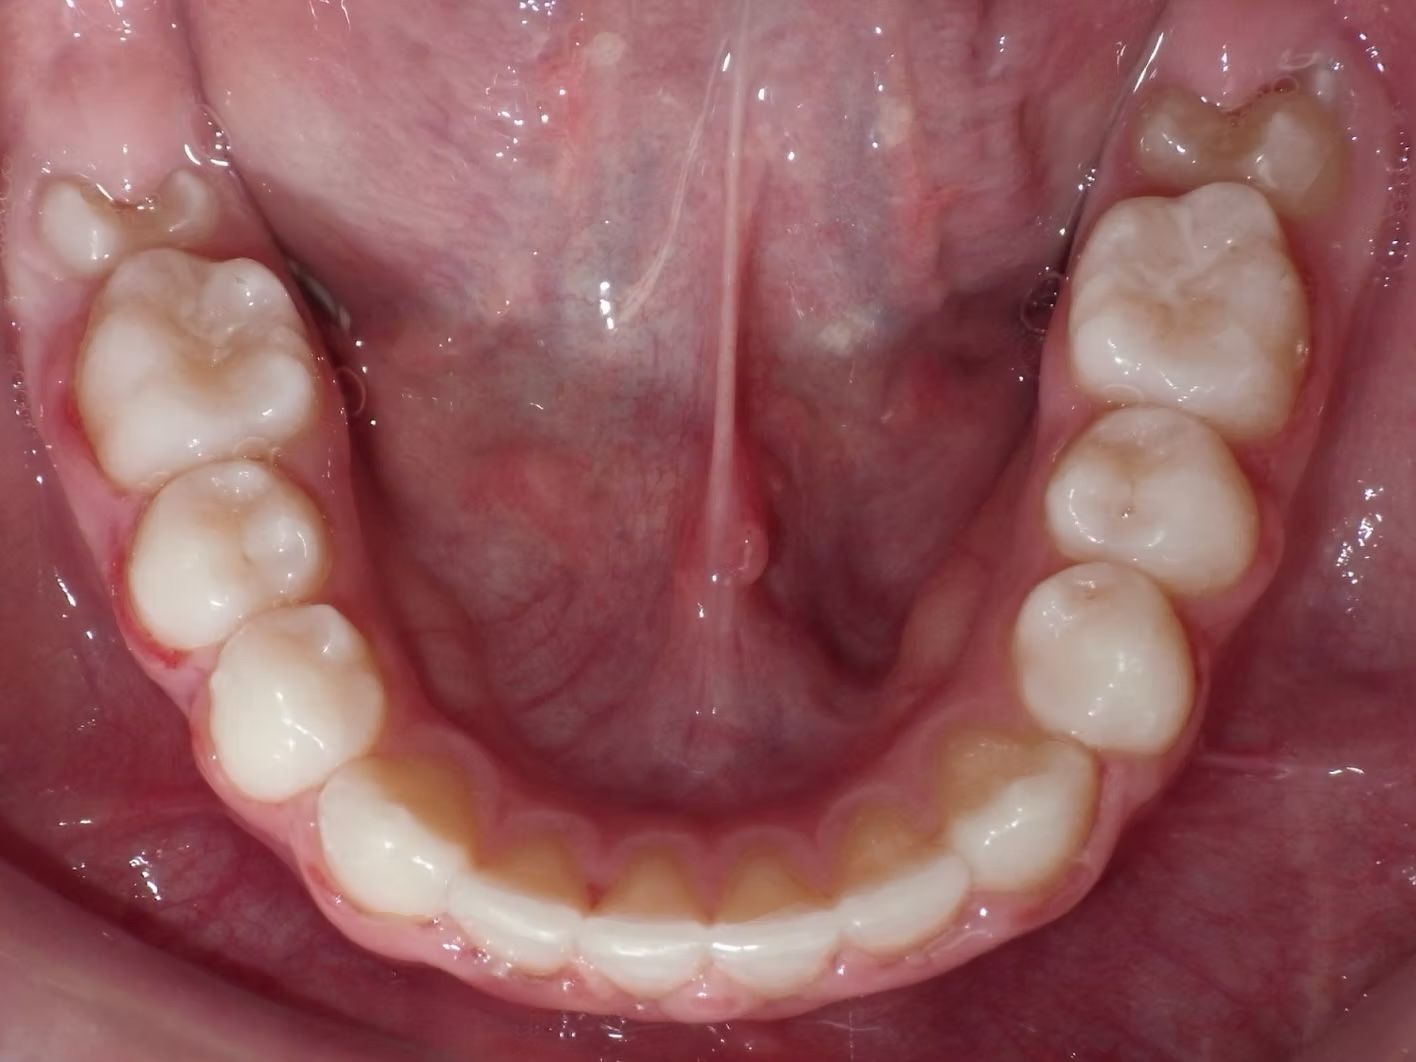

IAN

Ian came to the office because his lower teeth were crowded and he had an anterior cross bite. With traditional braces we resolved the crowding and aligned the teeth without causing flaring of the incisors and giving him a handsome smile. The treatment lasted 18 months and the final photos are at a 2 year follow up when we made him a new clear retainer.